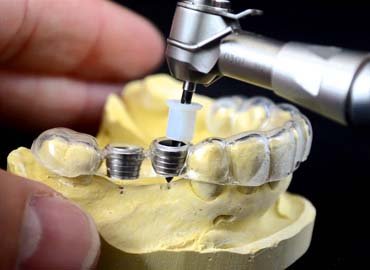

Guided implant dentistry

Even today, dentist are still typically trained to perform tooth implant placement without a computer guide. This conventional method would often require more time, processes, and incisions to complete the work. Consequently, for some patients, this could also lead to additional downtime following the surgery.

Yet, with computer-guided implant technology, dentists are able to better place the implant in the precise location. Advanced equipment and screens allow dentists to clearly see available bone, surrounding tissues, and where to safely install the implant. With such technology, more patients can now receive implants as an option compared to traditional methods. This is especially the case for patients who need multiple dental implants.